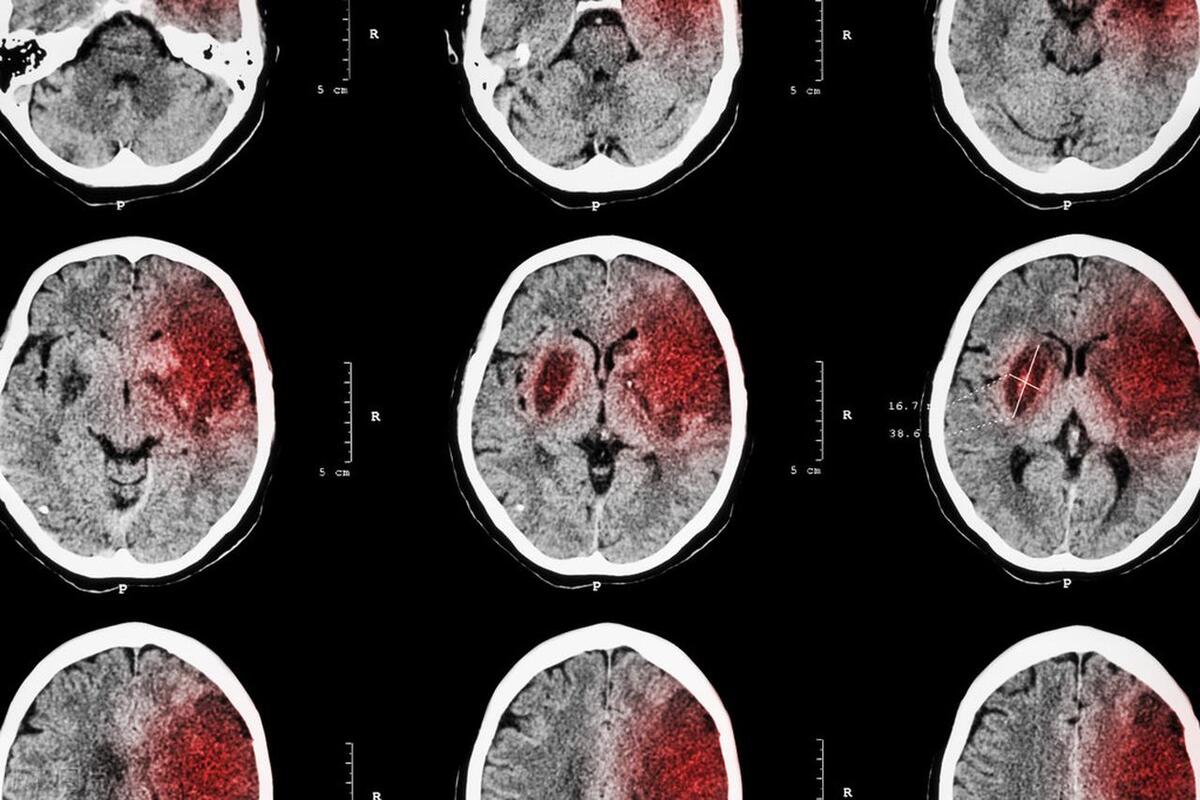

治疗大脑出血和脑梗这两种常见脑病,到底要怎么做?

大脑出血和脑梗是最常见的脑疾病,一个是血管破裂出血,一个是血管堵塞造成供血不足。虽然情况不同,但治疗的原则有几个大方向是一致的。